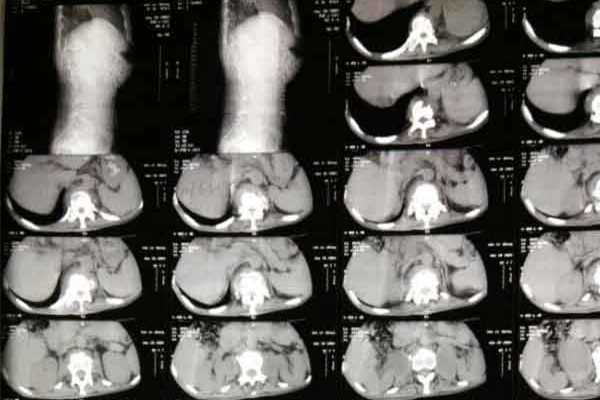

骨结核是常见病多继发于肺,该病全称又叫做骨与关节结核,是结核病的一种,由结核杆菌侵入骨或关节而引起的化脓性破坏性病变。那么骨结核怎么治疗呢?目前临床来看优先会选择抗结核药物治疗,但由于药物的副作用比较大患者无法耐受,于是现在专家就建议采取中医治疗,那么骨结核中医怎么治疗呢?

骨结核因为其病发于骨或关节,会消耗气血津液,致使后期形体嬴瘦,正气衰败,反复难愈,故名骨痨。又因本病成脓之后,可流窜他处形成寒性脓肿,破溃后脓液中伴败絮状痰样物,故又名流痰。中医治疗骨结核一般需要先由医生结合患者病情辩证,再根据证型制定用药方案。